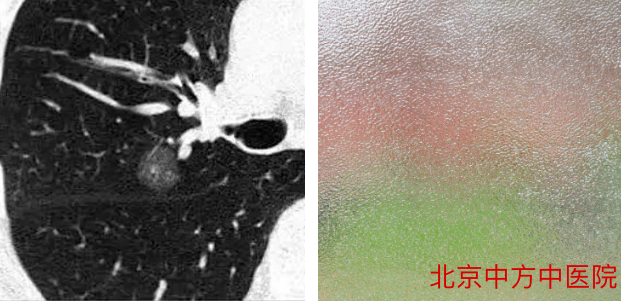

1、磨玻璃结节

在肺中有一些密度比较低的像磨渣样的玻璃,或者类似云雾一样的、小片状的、比较局限的结节,或者有时像一团小棉花一样的结节。(如左图)

就像我们的磨玻璃一样,能隐隐约约看到玻璃后面的场景,所以叫磨玻璃结节。(如右图)